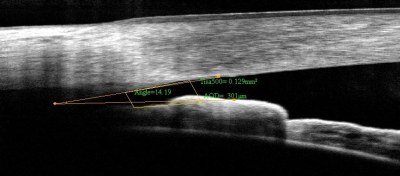

Η ενδοφθάλμια πίεση δημιουργείται από το υγρό που γεμίζει το πρόσθιο τμήμα του ματιού και ονομάζεται υδατοειδές υγρό. Αυτό το υγρό παράγεται πίσω από την ίριδα σε μια περιοχή που ονομάζεται ακτινωτό σώμα. Το υγρό αυτό δια μέσω της κόρης έρχεται εμπρός από την ίριδα και κινείται προς την περιοχή που σχηματίζεται από τον κερατοειδή (το διαφανές παράθυρο του ματιού) και την ίριδα ,την γωνία του ματιού, απ’ όπου και αποχετεύεται. Στα φυσιολογικά μάτια υπάρχει ισορροπία μεταξύ του παραγόμενου και του αποχετευόμενου υγρού. Όταν αυτή η ισορροπία διαταράσσεται, λόγω συνήθως μείωσης της αποχέτευσης, τότε αυξάνεται η πίεση στα μάτια.

Πρωτοπαθές γλαύκωμα ανοιχτής γωνίας, πρωτοπαθές γλαύκωμα κλειστής γωνίας, δευτεροπαθές γλαύκωμα και συγγενές γλαύκωμα.

H θεραπεία με LASER είναι κατάλληλη μόνο για ορισμένους τύπους γλαυκωμάτων. Υπάρχουν δύο κύριοι τύποι LASER θεραπείας. H ALT (Argon Laser Trabeculoplasty) και η SLT (Selective Laser Trabeculoplasty). Eπίσης το LASER μπορεί να χρησιμοποιηθεί σαν προληπτική θεραπεία σε περιπτώσεις στενής γωνίας (LASER IRIDOTOMY) για αποφυγή κρίσης οξέως γλαυκώματος.